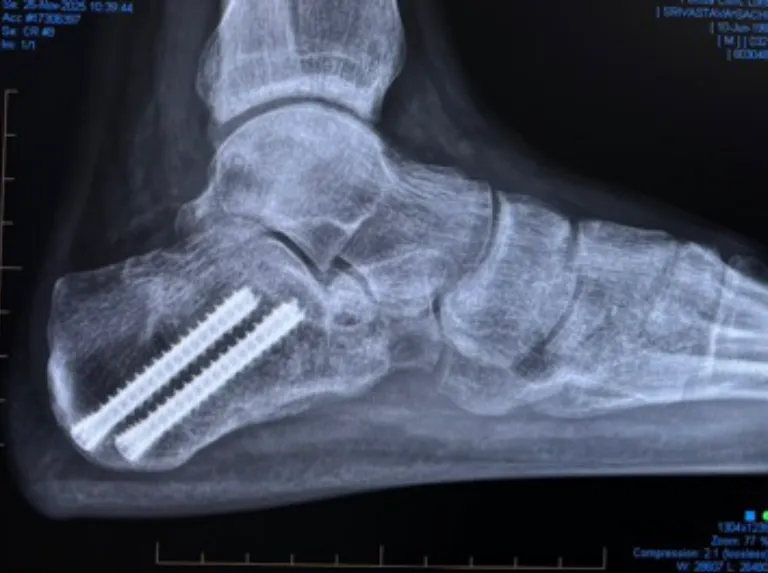

Arthroscopic Calcaneal Fixation

Arthroscopic fixation is a minimally invasive technique that I developed and have used at the Imperial Major Trauma Centre for over 15 years.

This method combines:

- Percutaneous fracture reduction

- Arthroscopic visualisation of the subtalar joint

- Precise restoration of the joint surface under direct vision

Key advantages include:

- Minimal soft-tissue trauma

- Ability to operate immediately, without waiting for swelling to subside

- Lowest infection risk of all approaches

- Rapid wound healing

- Early physiotherapy, typically from 1 week post-operatively

- No plaster cast required

This technique is particularly beneficial in displaced 2-part or 3-part fractures where joint surface accuracy is critical.

Post-operative Course

- Immobilisation in a protective orthopaedic boot

- Physiotherapy starts at 1 week

- Non-weight bearing for 4 weeks

- Light weight bearing during weeks 4–6

- Full weight bearing from 6 weeks onwards

Most patients return to normal daily activities by 10–12 weeks, though swelling and discomfort may persist. Light sporting activity is typically possible from 16 weeks.